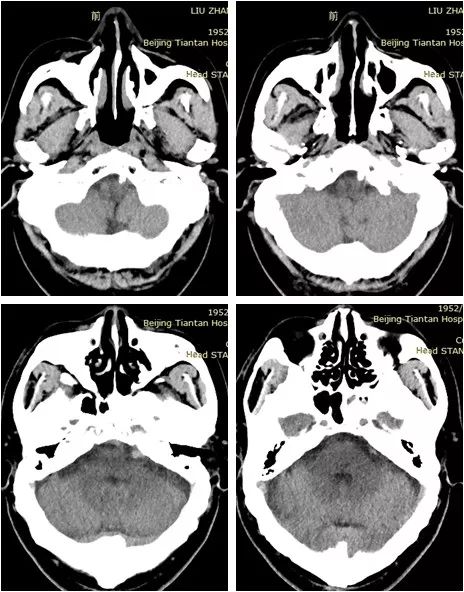

患者20余天前感右上肢麻木无力,因程度轻,未予重视。10余天前出现头晕,伴站立不稳,持续约1分钟后自行好转。病后就诊当地医院行头MRI:脑桥区新鲜梗死(图1)。

术后即刻头CT:未见出血(图11)。

图11